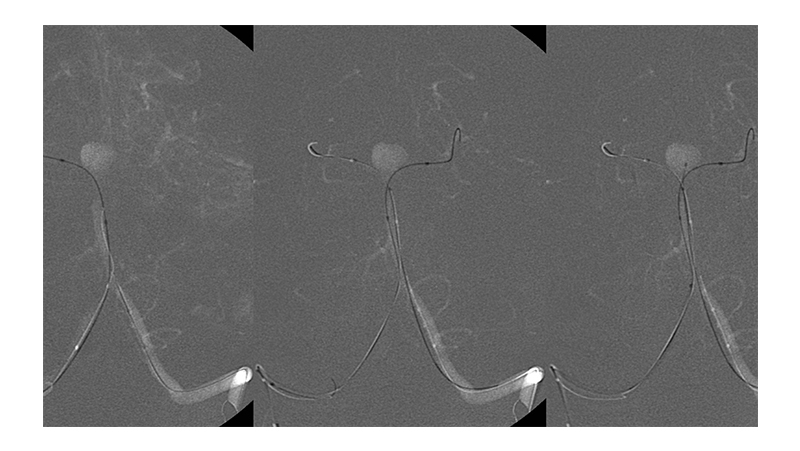

Εικόνα 4: Τοποθέτηση δύο μπαλονιών μπροστά στον αυχένα του ανευρύσματος, από το ανώτερο τριτημόριο της βασικής, στο Ρ1 των οπισθίων εγκεφαλικών αρτηριών εκατέρωθεν. Ο μικροκαθετήρας γιά τον εμβολισμό έχει τοποθετηθεί μέσα στον σάκκο του ανευρύσματος (δεξιά εικόνα).

Εικόνα 5: Με φουσκωμένα τα δύο μπαλόνια γίνεται η τοποθέτηση των μεταλλικών σπειραμάτων και η πλήρωση του ανευρύσματος. Η πρόπτωση των coils προς το θυγατρικό αγγείο αποτρέπεται από την παρουσία των μπαλονιών προστασίας.

Εικόνα 9: Το εκμαγείο των coils μετά τον εμβολισμό.